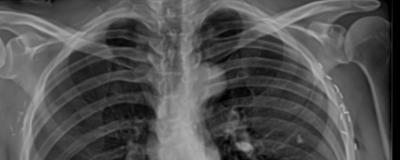

Radiography showed that the patient had a left lumbar scoliosis that measured 73 degrees and had a sagittal imbalance of 18cm (forward leaning posture). Based on her prior scans her spinal deformity had progressed over the past few years.

Standing X-ray viewed from the backside showing the 73 degree left sided scoliotic curve. Note the right sided ribs rubbing on the pelvis.